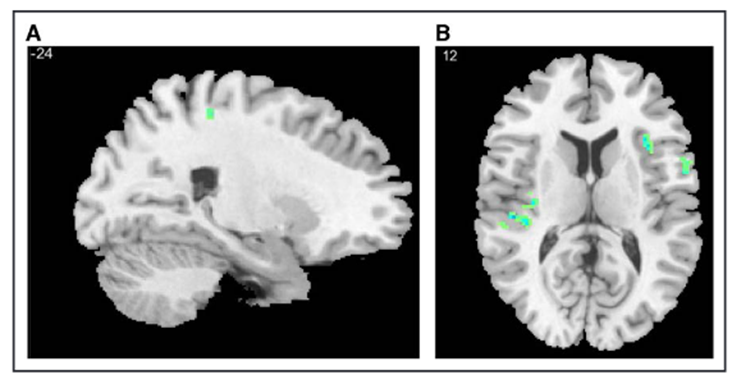

4.3 健康对照组自愿收缩的充盈期(P4P5)与休息对比

在健康对照组中,P4_VOL与休息的对比显示多个区域显著激活,包括右侧岛叶、双侧背侧ACC、中部扣带回、右侧背外侧前额叶皮质(DLPFC)和左侧初级体感皮质(图3)。在P5_VOL与休息的对比中,差异有所减弱,但在右侧岛叶、右侧DLPFC、左侧下额回和左侧初级体感皮质中仍存在差异(图3)。

健康参与者意志性逼尿肌收缩前的大脑活动图

健康参与者在自主逼尿肌收缩前P4(顶部,AC)和P5(底部DF)期间血氧水平依赖性(BOLD)效应变化的代表性矢状面和轴向图像。注意P4期头端前扣带皮层(AB)和岛叶(C)的激活。注意P5BOLD效应的衰减,岛叶(F)中的BOLD效应持续存在。